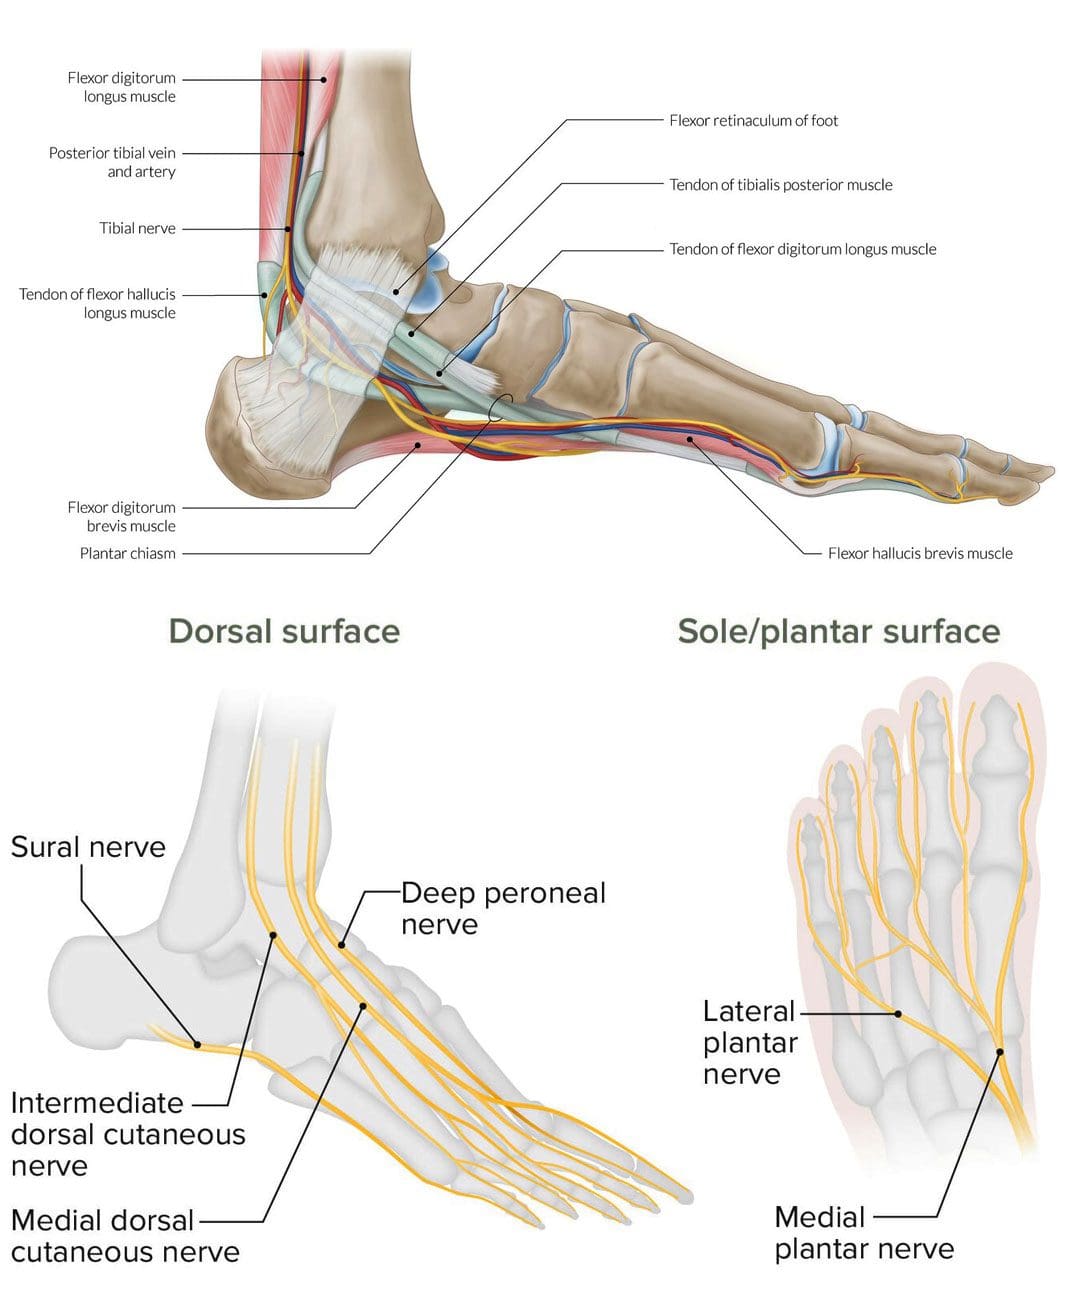

Анатомия голеностопа: Сухожилия и их строение